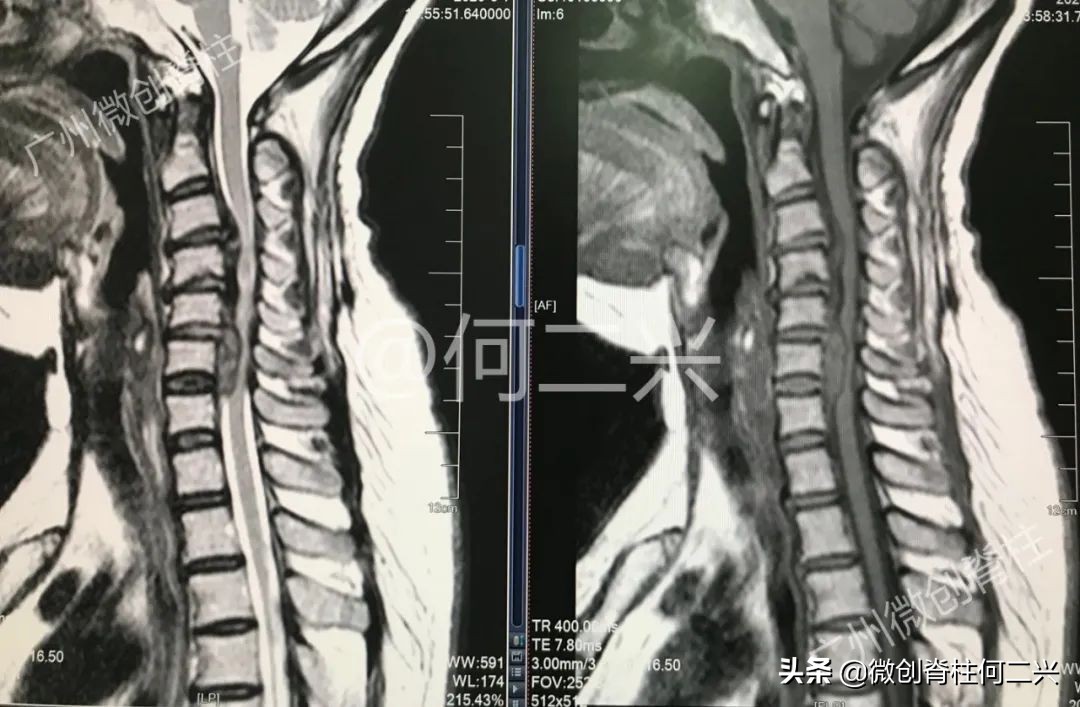

原来,患者颈椎脊髓神经被来自前方的病变严重压迫,脊髓最窄的地方只剩正常的四分之一。医学难题一个又一个的摆在何教授面前:

- 病变特殊:范围广,由第三颈椎开始,一直到第七颈椎,波及整整4个椎间隙共5个脊椎;

- 病变的性质也不明确,其中有大块的椎间盘组织脱落压迫,但椎体后缘又有连续的异常增生的后纵韧带;

- 脊髓神经的功能已经严重受损,手术的干扰很容易导致病情加重;